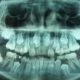

Tecnica Transmucosa

No. Esiste anche la tecnica transmucosa (flapless), che non utilizza il bisturi e non vi è bisogno di punti di sutura, semplicemente si fa un piccolo foro sulla gengiva per far passare l’impianto.

Non vi è alcuna differenza sulla durata nel tempo degli impianti inseriti con la tecnica transmucosa rispetto a quelli inseriti con la tecnica tradizionale, l’unica differenza tra le due tecniche è che la tecnica tradizonale è molto invasiva e comporta grandi traumi e sacrifici, mentre la tecnica transmucosa è una tecnica minimamente invasiva quindi piu’ “leggera” per il paziente.